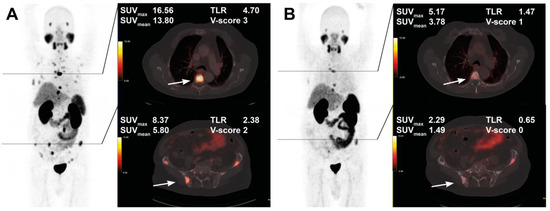

The course of all lesions per patient is depicted in Figure 3. In 11 patients showing lesion response in included baseline tumor sites, ≥2 new onset lesions on posttherapeutic imaging led to discontinuation of RLT. Examples of intraindividual lesion response on [68Ga]Ga-PSMA-11 PET/CT imaging are provided in Figure 4 and Figure 5.

Figure 4. Treatment response in a 76-year-old patient after 4 cycles of RLT with cumulative 32.0 GBq [177Lu]Lu-PSMA-617. Maximum intensity projection (MIP) images (left) with cross-section fusion images in a thoracic and pelvic plane at baseline (A) and after RLT (B). Lesions (white arrows) show response to RLT, with the upper lesion in the thoracic spine maintaining detectable residual activity.